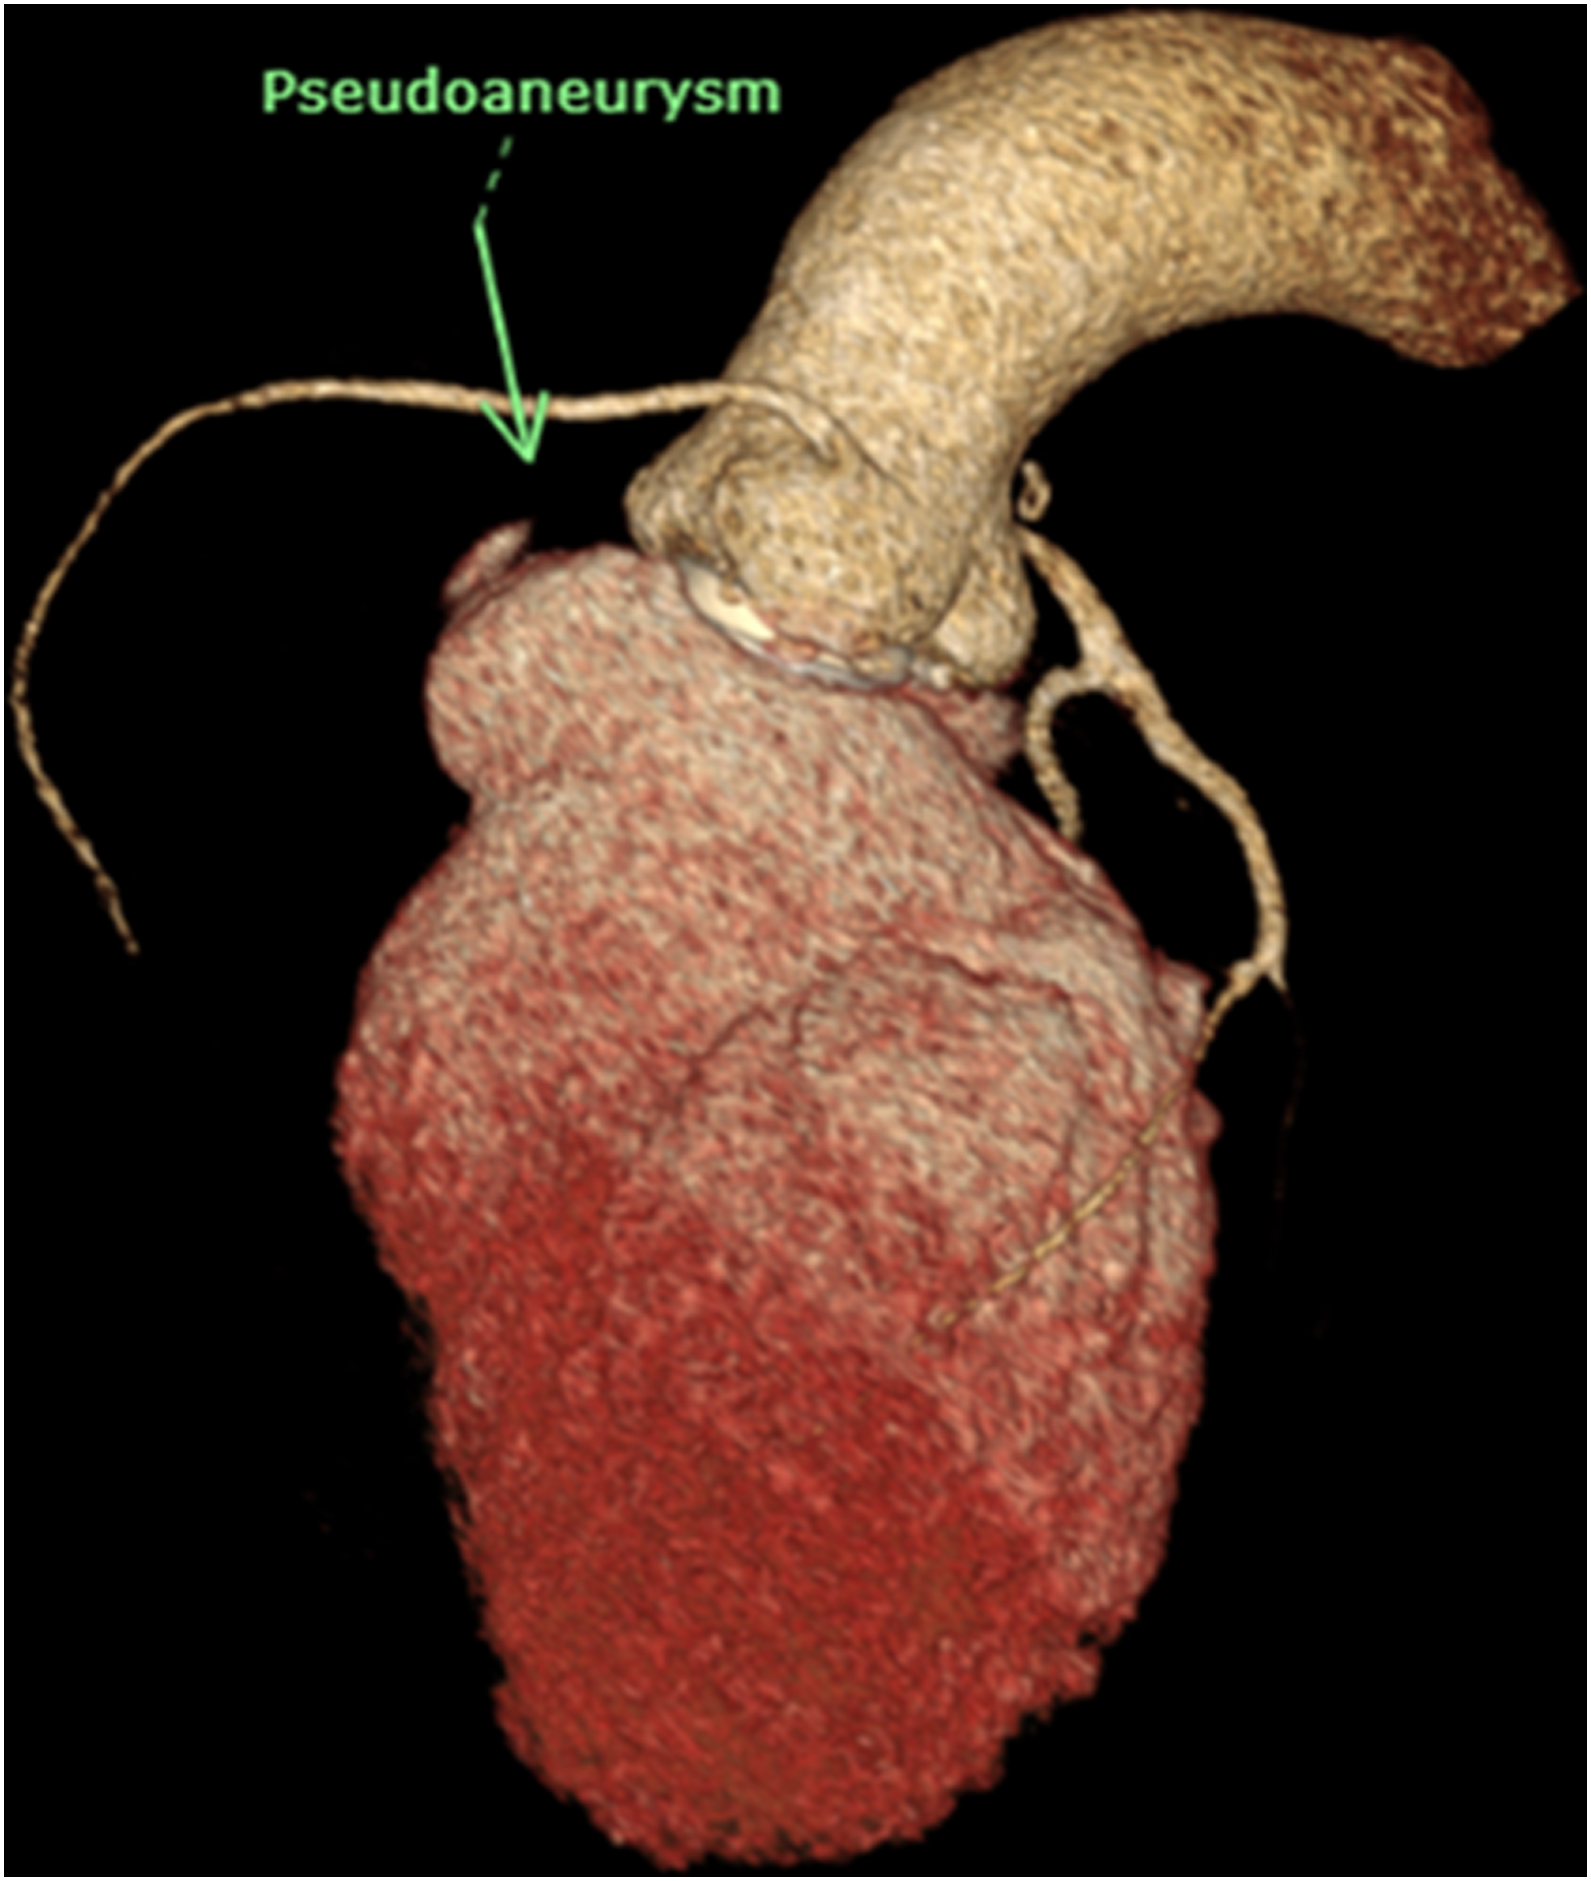

CT cardiac revealed pseudoaneurysm of the aortomitral intervalvular fibrosa with laminated thrombus with no LAA thrombus visualized.